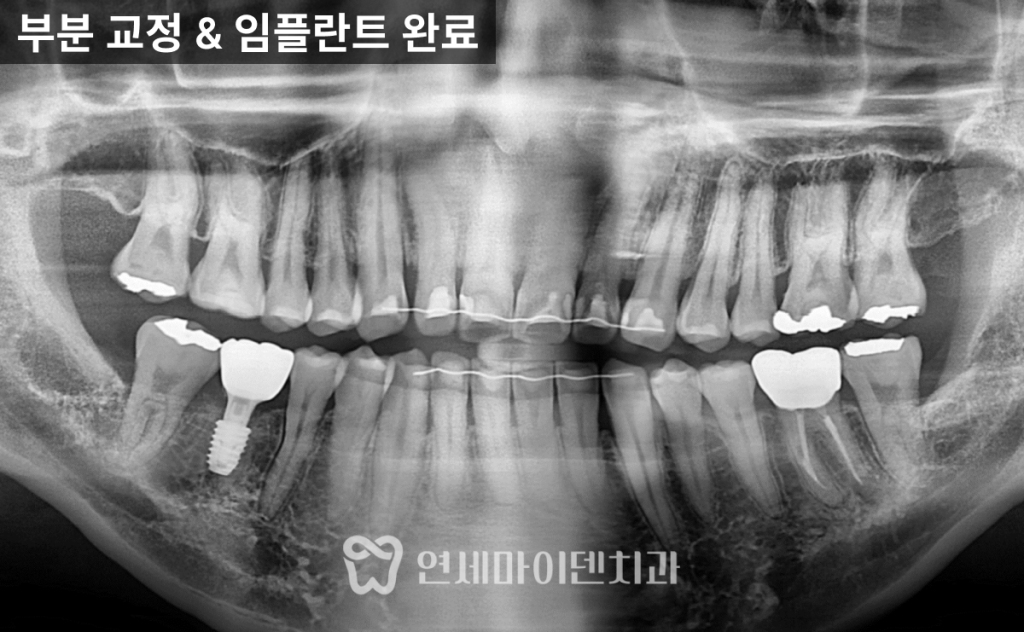

파노라마 사진을 통해 확인한 결과,

- 6번 치아 부위의 공간이 심하게 좁아져 있었으며

- 위아래 사랑니는 모두 자라 있었고, 일부는 충치가 심했습니다.

임플란트 식립

공간 확보 후에는 6번 어금니 부위에 임플란트를 식립하였고,

약 2~3개월간의 안정화 기간을 거쳐

뼈와 임플란트가 단단히 결합되었습니다.

최종적으로는

- 임플란트 크라운이 완성되었고,

- 교합과 주변 치아의 움직임 없이 안정적인 결과를 얻을 수 있었습니다.

또한 왼쪽 아래 어금니의 재신경치료 부위 염증도 호전되어,

전체적인 구강 상태가 크게 개선되었습니다.